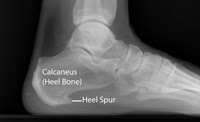

Đôi khi X-quang hoặc MRI có thể được đề nghị để loại trừ các vấn đề khác, chẳng hạn như gãy xương hoặc đau do chèn ép thần kinh.

Có khi X-quang cho thấy gai xương gót chân (heel spur).

Gai gót chân (hay cựa gót chân) là do sự lắng đọng calcium tạo thành mẩu xương nhỏ nhú lên ở mặt dưới của xương gót chân.

Quá trình này xảy ra trong nhiều tháng (> 6 tháng ), do sự kéo căng của cơ và dây chằng vùng chân, cân gan chân, làm rách màng bao xương gót lặp đi lặp lại. Thông thường cân gan chân bị thương tổn sẽ được chữa lành thông qua hoạt động của nguyên bào sợi trong vòng ít nhất sáu tuần. Nếu chấn thương vẫn tồn tại vượt thời gian này, nguyên bào tạo xương được huy động vào khu vực này và kết quả cuối cùng là sự vôi hóa tạo gai xương.

Trước đây, các gai xương thường được qui cho là gây đau gót chân và được phẫu thuật cắt bỏ. Các nghiên cứu thấy rằng gai gót chân xuất hiện ở khoảng 50% bệnh nhân có triệu chứng và 20% bệnh nhân không có triệu chứng đau gót chân. Nhiều bệnh nhân bị viêm cân gan chân không có gai gót chân, và cũng rất nhiều người có gai xương gót mà không đau gót chân. Vì thế, ngày nay người ta cho rằng gai gót chân không phải là nguyên nhân gây ra các triệu chứng của viêm cân gan chân, đúng hơn, nó là hậu quả của tiến trình này; do đó, không cần điều trị hoặc loại bỏ.

Gai gót chân thường dễ thấy trên phim Xquang chụp nghiêng bàn chân.